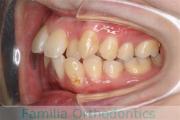

八重歯を治したいということで来院されました。下あごの左ずれのある上顎前突(出っ歯)・叢生(でこぼこ)でしたので、上は左右から、下はで左のみ小臼歯を抜歯して、歯科矯正用アンカースクリューとマルチブラケット法にて治療を行いました。2年強、30回程度の通院が必要でした。

上下とも前歯の叢生(でこぼこ、凹凸、ガタガタ)があるため、保定を怠ると後戻りのリスクがあります。